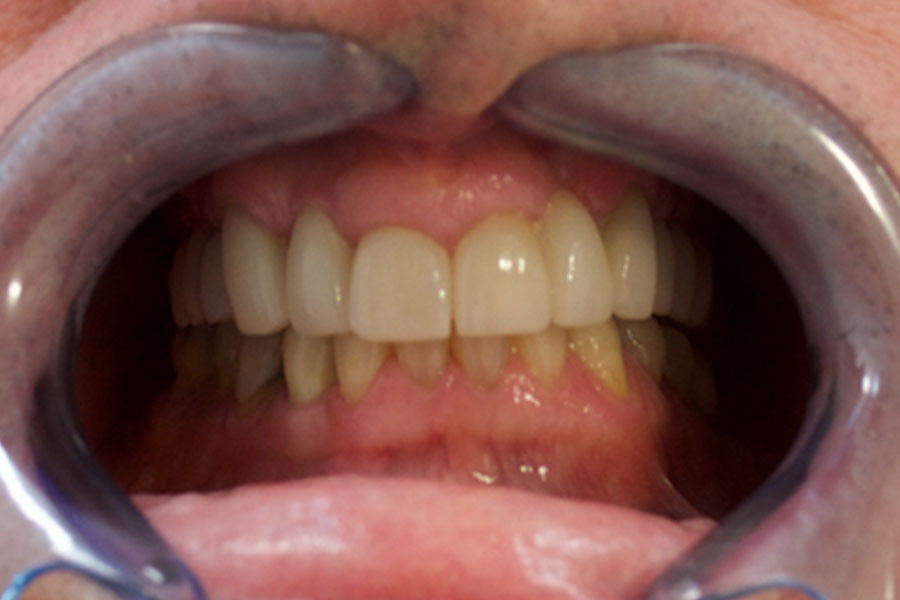

Phil was wearing a removable partial denture for many years.

As he lost some more teeth the pasrtial denture became less stable. Chris finally decided to have dental implants his missing teeth.

Two implants were utilised to support a bridge where there were three missing teeth in a row. His existing natural teeth received crowns and veneers as reinforcements and also to match the highly esthetic implant crowns and bridges.